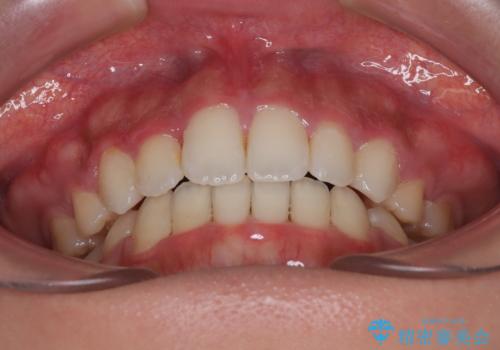

- 口元の突出感と口の閉じにくさを気にして来院された患者様です。

上下左右第一小臼歯4本を抜歯し、ワイヤー装置にて口元を引っ込めるよう矯正治療を行うこととしました。

口元の突出感が改善されてことで、下唇に引っかかっていた上顎前歯も気にならなくなりました。